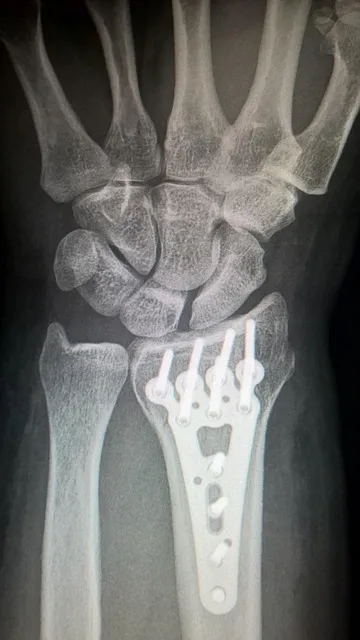

治疗骨折的方法多种多样,需要根据骨折的类型、程度以及患者的整体健康状况选择合适的治疗方案。对于肱骨近端骨折,常见的治疗方式包括手术固定和非手术治疗。手术固定一般适用于严重的骨折,通过内固定物如钢板、螺钉等将断骨对位固定,从而促进骨愈合。而对于较轻微的骨折,可选择佩戴支具或石膏固定,让骨折自行愈合。